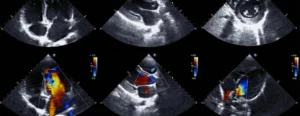

اکو قلب یا اکوکاردیوگرافی آزمایشی غیرتهاجمی و بدون درد است که با امواج صوتی، تصویر زنده و دقیقی از ساختار و کارکرد قلب فراهم می کند. چون قلب پیوسته منقبض می شود و هماهنگی بخش های آن حیاتی است، پزشک برای ارزیابی واقعی به چنین تصویربرداری پویایی نیاز دارد. با اکو می توان اندازه حفره ها، قدرت پمپاژ، وضعیت دریچه ها، جریان خون، فشار ریوی و وجود مایع اطراف قلب را سنجید و علت علائم را بهتر فهمید. در این مقاله، موارد قابل تشخیص در اکو، نکات گزارش، انواع روش ها و کاربردشان، محدودیت ها، آمادگی لازم و بهره گیری بهینه از نتایج بررسی می شود.

اکو قلب یک آزمایش غیرتهاجمی و بدون درد است که با استفاده از امواج صوتی، تصویری از ساختار و عملکرد قلب ایجاد میکند. این روش به پزشکان کمک میکند تا از سلامت کلی قلب، عملکرد دریچهها و جریان خون در بدن اطلاعات دقیقتری کسب کنند.

اکو از امواج فراصوت استفاده می کند. پروب روی قفسه سینه یا در برخی شرایط در مسیر مری قرار می گیرد و انعکاس امواج از بافت های قلبی به تصویر تبدیل می شود. این تصویر زنده است و پزشک می تواند حرکات دریچه ها، ضخامت دیواره ها، باز و بسته شدن پرده ها و حتی سرعت جریان خون را ببیند و اندازه گیری کند. به همین دلیل وقتی می پرسیم در اکو قلب چه چیزهایی مشخص می شود؟ پاسخ، ترکیبی از اندازه گیری های دقیق و مشاهده های کیفی است.

الگوی جریان خون با داپلر

- اندازه گیری سرعت و جهت جریان برای محاسبه شدت نارسایی یا تنگی دریچه ها

- محاسبه جریان از مسیرهای مشخص که در تصمیم درمانی بسیار کاربردی است